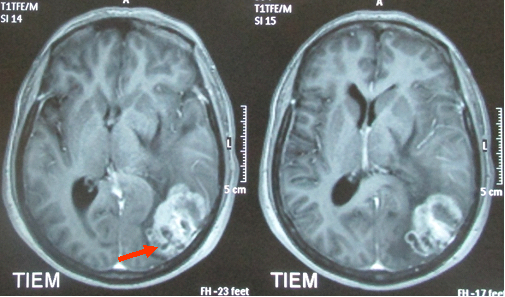

• MRI sọ não cho thấy khối u vùng chẩm trái kích thước (3,5x5)cm ngấm thuốc sau tiêm, có phù não xung quanh (hình 2).

Hình 2: Hình ảnh chụp MRI sọ não cho thấy khối u vùng chẩm trái, kích thước (3,5x5)cm ngấm thuốc sau tiêm,có phù não xung quanh.

Trước điều trị

Sau điều trị 4 tháng